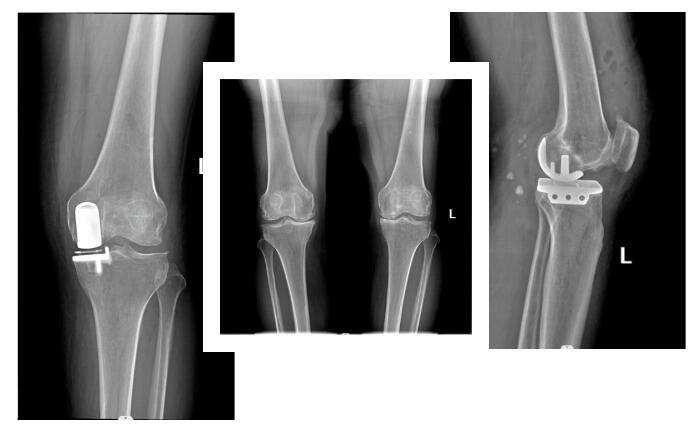

����5�����ǿƽ��\��һ��96�q���g�y�����ۻ�������(j��)�˽⣬�����ڼҲ�С�Ļ��������F(xi��n)���y����ʹ������֫�̿s����?y��n)��½o��Ů���韩�������ڼ���Ϣ���S�������L���P�����β����F(xi��n)����e�쯏����ʹ������ݚ�D(zhu��n)����t(y��)Ժ�������R���g(sh��)�L(f��ng)�U(xi��n)���ί��y�ȴ����ί��o������K��ͬС�^(q��)���ӽ��h������ŮĽ����������A���t(y��)Ժ�ǿ������ҵ�������ξ��\��ͨ�^Ӱ��z�����Y(ji��)���@ʾ�����҂�(c��)�ɹ��i��������Ԕ��(x��)���w�˽��������w��r������ν��h�����_չ���҂�(c��)�˹��ɹ��^�ÓQ�g(sh��)��Super CAP������

Super CAP�^���y(t��ng)�˹��ɹ��^�ÓQ��·�ă�(y��u)�c(di��n)����1���п�С: �п��L�ȼs6 cm�����y(t��ng)���(c��)��·��15cm�������g(sh��)��(chu��ng)���^������2���g(sh��)���@¶����������g(sh��)�г�Ѫ�^�٣�50ml���o���ù����������y(t��ng)��·�g(sh��)�м��g(sh��)���Ѫ700-1000ml������3���g(sh��)��֏�(f��)�����g(sh��)��(d��ng)������6С�r(sh��)���´������5-7��ɳ�Ժ�����ڿs�����P����סԺ�r(sh��)�g������������o(h��)���ɱ��ͻ��ߵĽ�(j��ng)��(j��)ؓ(f��)��(d��n)����4���g(sh��)���˹��P(gu��n)��(ji��)����Óλ�����y(t��ng)��·�O���װl(f��)���P(gu��n)��(ji��)Óλ����

��(j��ng)�^����(f��)���]��������߀�ǛQ������t(y��)��������g(sh��)��������Ύ��I(l��ng)�ǿƈF(tu��n)�(du��)���������������g(sh��)�����ذY�t(y��)�W(xu��)�����ă�(n��i)����������(n��i)���ڿƵȶ��W(xu��)�ƈF(tu��n)�(du��)�Ĺ�ͬ�f(xi��)�������ɹ��؞����ˌ�(sh��)ʩ���҂�(c��)�˹��ɹ��^�ÓQ�g(sh��)��Super Cap�������g(sh��)�ڶ���������ʹ���������´�����������g(sh��)��7�쿵��(f��)��Ժ��2���µĻ��L���҂���֪�����ˬF(xi��n)���ѽ�(j��ng)�܉�Ó�x���������ɻ������

����6�·ݣ�����������M(j��n)�������y�����ۻ��߿��ٿ���(f��)������ͬ�r(sh��)�����g(sh��)�ҡ������Ƽ����P(gu��n)��(n��i)�����o�����ҷe�O������������\��Ժ�����F(tu��n)�(du��)���������u�������r(sh��)�_չ���g(sh��)�����g(sh��)�п�С��סԺ�r(sh��)�g���������������껼�ߵ������|(zh��)��������������ѽ�(j��ng)��20����90�q���ϵĸ��g���ߌ�(sh��)ʩ�����g(sh��)�����߾����g(sh��)�������Ժ�����������Ҳ�A���˻����ҌُV��ٝ�u(y��)��

���t(y��)23�����������ηe�O̽���̈́�(chu��ng)�£����L�y��ϥ���������P(gu��n)��(ji��)�ÓQ���y��ϥ�P(gu��n)��(ji��)�ÓQ�����g(sh��)������ϥ�������ס��y���P(gu��n)��(ji��)�������P(gu��n)��(ji��)�R��(chu��ng)�ί����_չ�P(gu��n)��(ji��)�R���g(sh��)20�꣬��Ӌ(j��)���g(sh��)�������^3000�����_չ�y��ϥ�����P(gu��n)��(ji��)�ÓQ���g(sh��)10��������Ӌ(j��)���g(sh��)�����_(d��)1000������